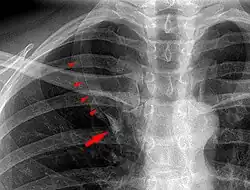

Azygos lobe on chest X-ray. Arrowheads show the delineation of the lobe. Arrow points to the azygos vein.